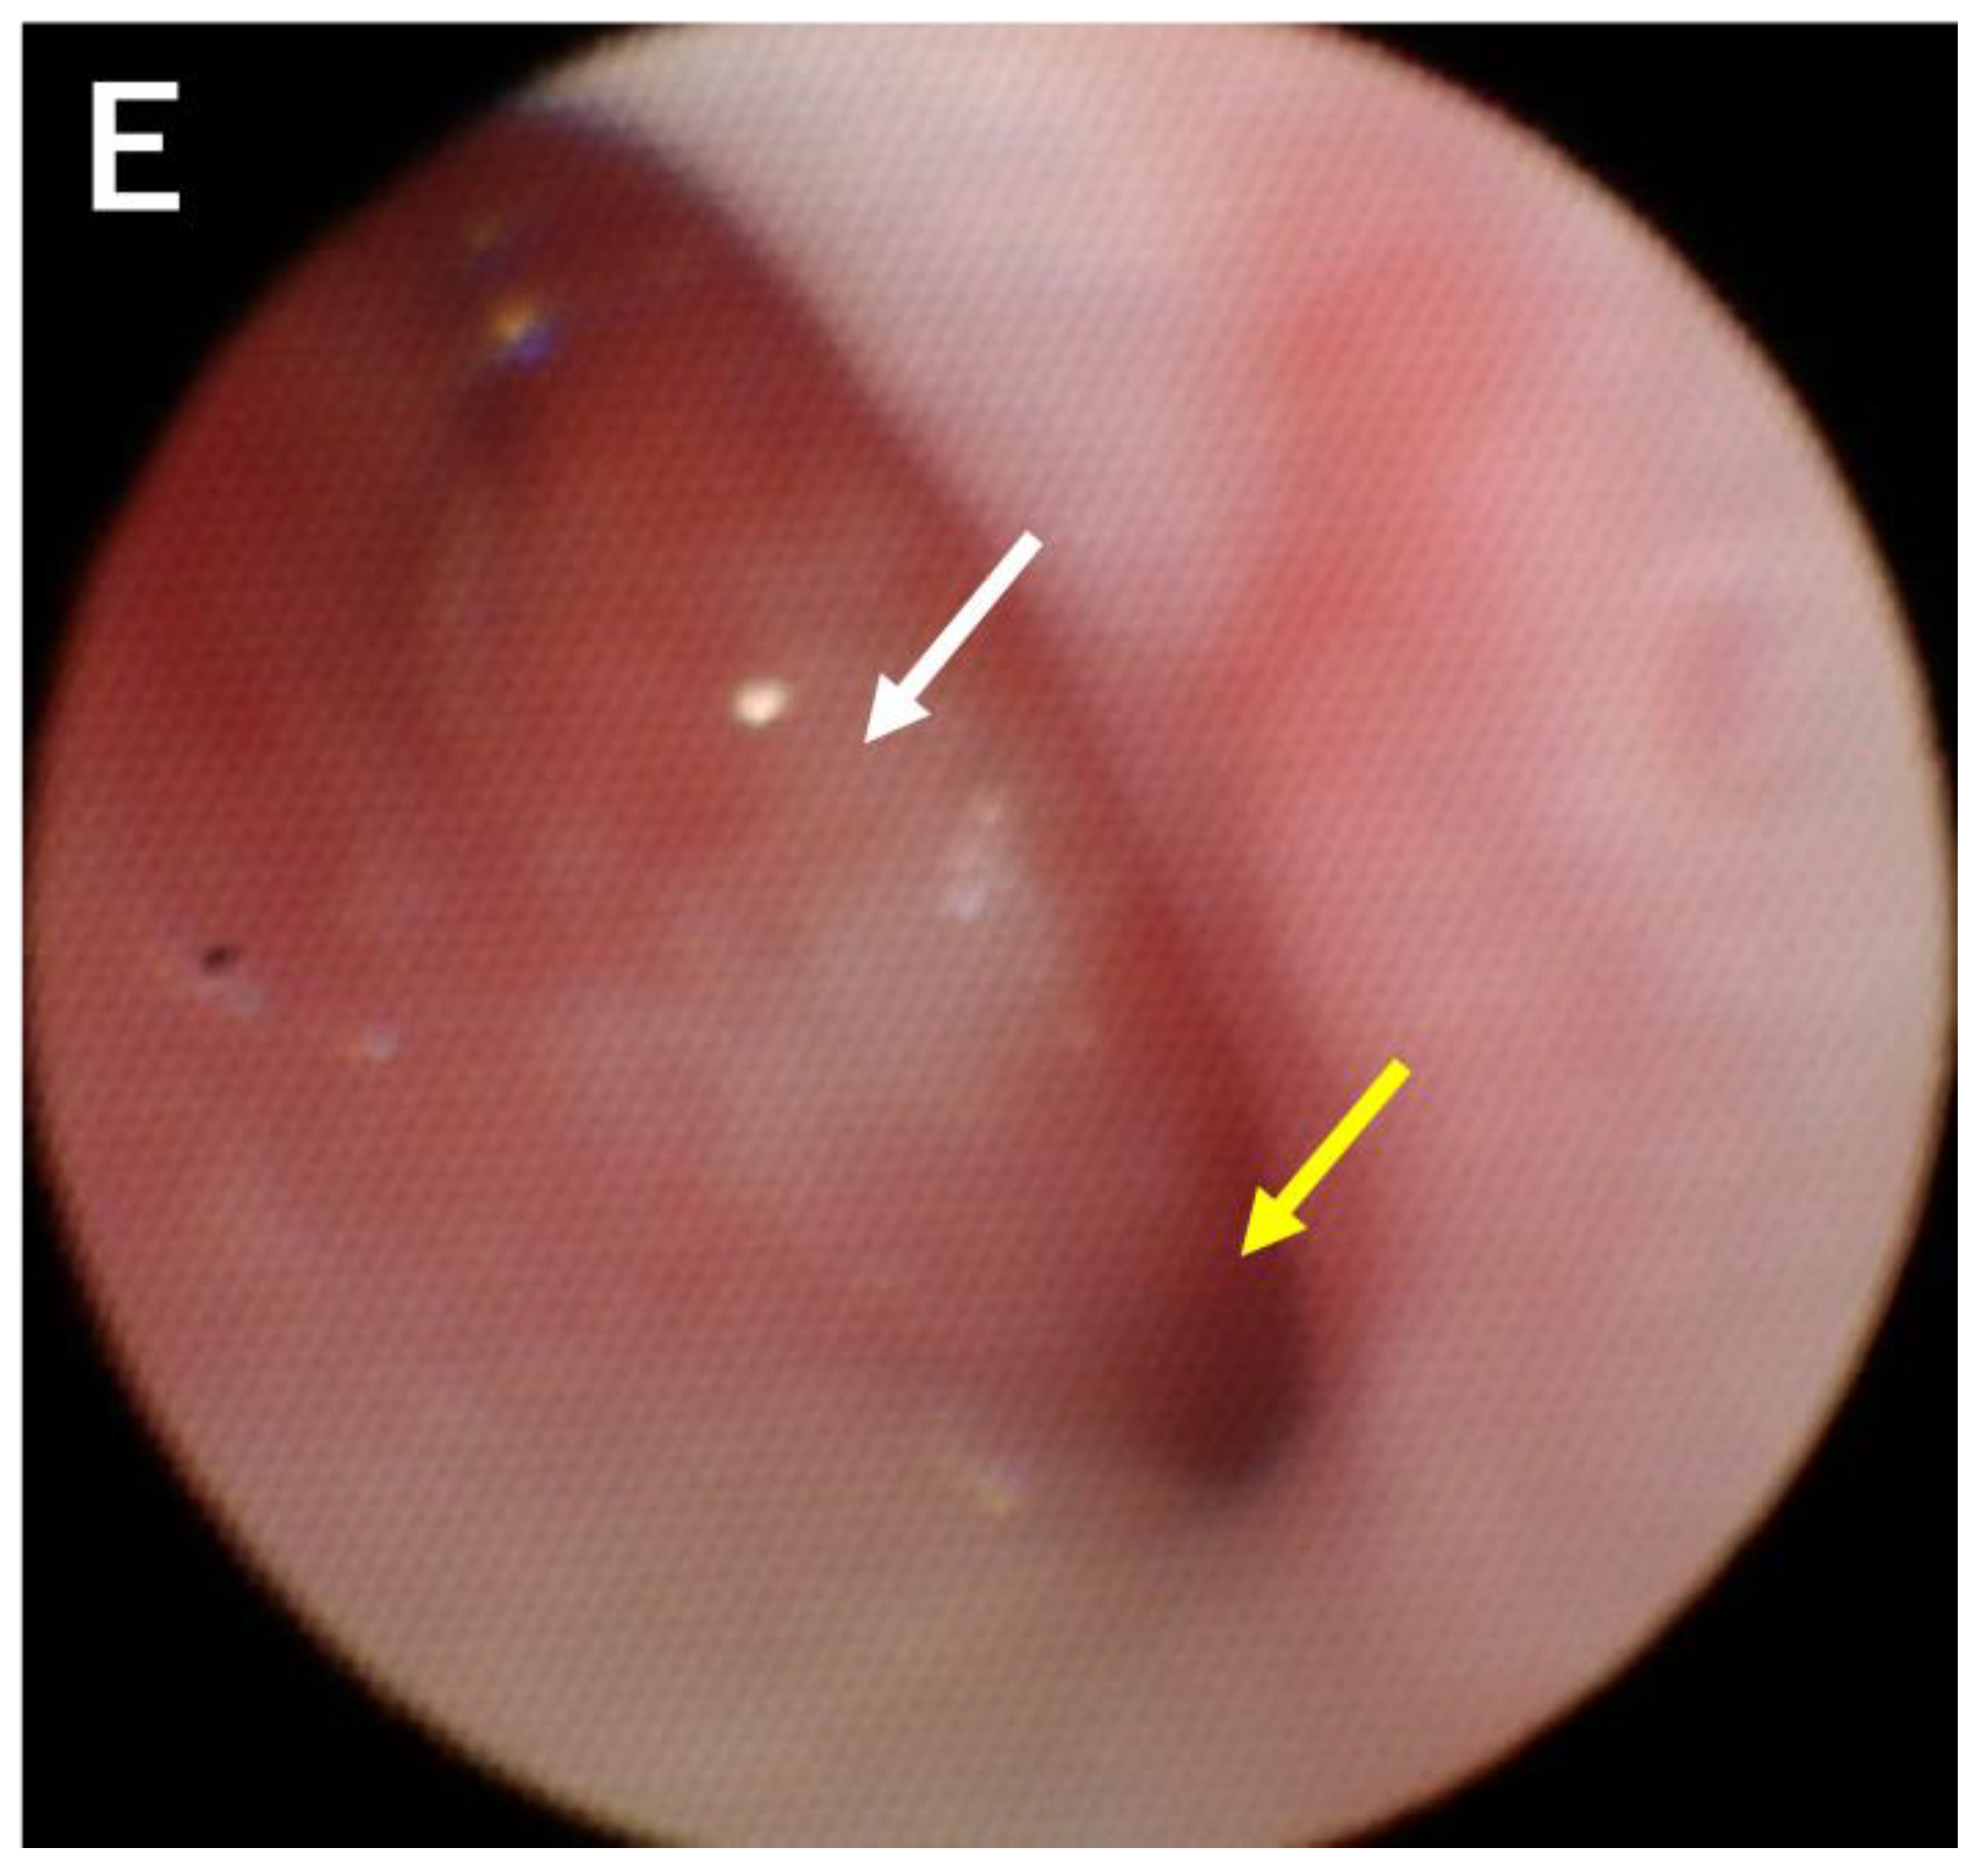

2. Case Description